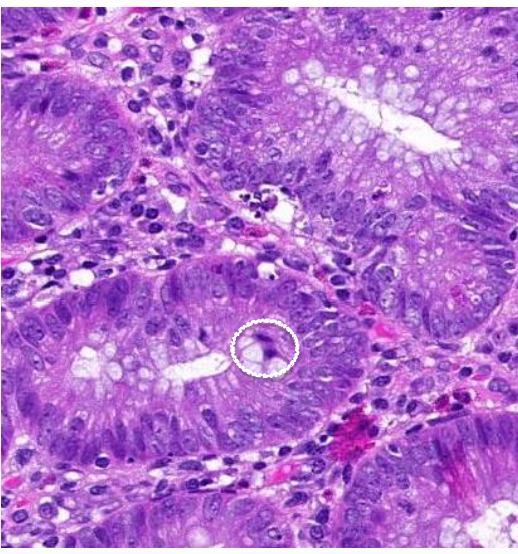

Welk preparaat

adenocarcinoom van het rectum/colon

pathologische kenmerken adenocarcinoom van het rectum/colon

abnormale klierbuizen

totaal verstoorde architectuur

polarisatie epitheel verloren: zware dysplasie

anisocytose & anisonucleose

mitose

pyknotische kernen

minder mucusproductie

necrosehaarden

infiltratie tot in spierlaag (muscularis externa)

wat wordt er aangeduid, rectum/colon

pyknotische kernen: onomkeerbare condensatie van chromatine in een kern die in necrose aan het gaan is

colon/rectum: wat wordt er aangeduid

debris van afgestorven cellen dat zich tumorducten gaat opstapelen